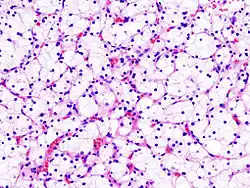

Micrograph of the most common type of renal cell carcinoma (clear cell)—on right of the image; non-tumour kidney is on the left of the image. Nephrectomy specimen. H&E stain

The gross and microscopic appearance of renal cell carcinomas is highly variable. The renal cell carcinoma may present reddened areas where blood vessels have bled, and cysts containing watery fluids.[64] The body of the tumour shows large blood vessels that have walls composed of cancerous cells. Gross examination often shows a yellowish, multilobulated tumor in the renal cortex, which frequently contains zones of necrosis, haemorrhage and scarring. In a microscopic context, there are four major histologic subtypes of renal cell cancer: clear cell (conventional RCC, 75%), papillary (15%), chromophobic (5%), and collecting duct (2%). Sarcomatoid changes (morphology and patterns of IHC that mimic sarcoma, spindle cells) can be observed within any RCC subtype and are associated with more aggressive clinical course and worse prognosis. Under light microscopy, these tumour cells can exhibit papillae, tubules or nests, and are quite large, atypical, and polygonal.

Recent studies have brought attention to the close association of the type of cancerous cells to the aggressiveness of the condition. Some studies suggest that these cancerous cells accumulate glycogen and lipids, their cytoplasm appear "clear", the nuclei remain in the middle of the cells, and the cellular membrane is evident.[65] Some cells may be smaller, with eosinophilic cytoplasm, resembling normal tubular cells. The stroma is reduced, but well vascularised. The tumour compresses the surrounding parenchyma, producing a pseudocapsule.[66]

The most common cell type exhibited by renal cell carcinoma is the clear cell, which is named by the dissolving of the cells' high lipid content in the cytoplasm. The clear cells are thought to be the least likely to spread and usually respond more favourably to treatment. However, most of the tumours contain a mixture of cells. The most aggressive stage of renal cancer is believed to be the one in which the tumour is mixed, containing both clear and granular cells.[67]